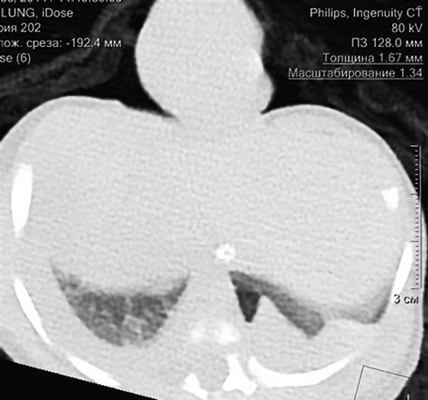

Девочке 2-х суток жизни выполнена МСКТ в условиях медикаментозной седации с проведением проспективной ЭКГ-синхронизации, болюсного внутривенного контрастирования (в/в) препаратом Визипак 270 в объеме 6 мл в периферическую вену правой нижней конечности. Сканирование осуществлено на аппарате Philips Ingenity 128, kv 80, mas 350, протяженность сканирования 250 мм. Выполнено обзорное сканирование грудной клетки и брюшной полости до контрастного усиления, по результатам которого определяется диффузная неравномерность пневматизации легочной паренхимы, с наличием участков ателектазированной легочной ткани в верхних и нижних долях легких с обеих сторон, в обеих плевральных полостях определяется умеренное количество выпота (рис. 3). Сердце визуализировано вне грудной полости (рис. 4). В грыжевом мешке определяется фрагмент паренхиматозного органа брюшной полости, по нативным денситометрических показателям идентичный паренхиме печени (50HU), как показано на рисунке 5.

Рис. 3. Мультиспиральная компьютерная томография, мультипланарная реконструкция (MPR) легких в корональной проекции, в просвете трахеи интубационная трубка, пневматизация легких диффузно неравномерная с наличием участков ателектазированной легочной ткани

Рис. 4. Мультиспиральная компьютерная томография (МСКТ) легких, аксиальная проекция, патологический выпот в обеих плевральных полостях, эктопия сердца на переднюю грудную стенку

Рис. 5. МСКТ брюшной полости, аксиальная проекция, визуализирован грыжевой мешок, содержащий правую долю печени